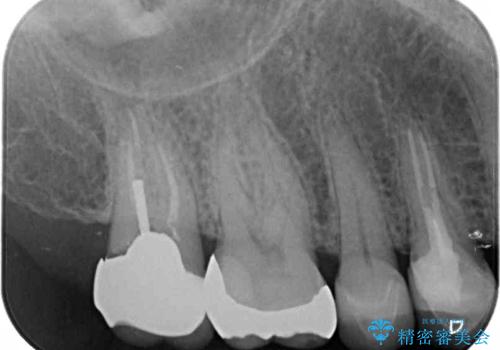

- 奥歯の間にものが挟まって不快であるとのことで来院された患者様です。

検査を行った結果、非常に強い咬合力により隣の歯との隣接面にひびが入り、虫歯が拡大している状態でした。

部分的にゴールドインレーが装着されていたので、虫歯と合わせて除去し、新たにゴールドインレーにて修復治療を行うこととしました。